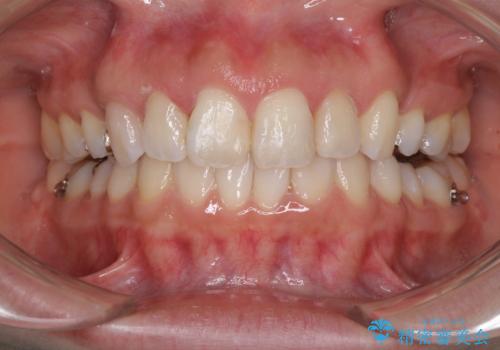

インビザラインにて抜歯矯正を行うと、高頻度で奥歯が咬み合わなくなります。

抜歯スペースが閉じてからも咬みにくさ改善のためマウスピース矯正を継続するため、治療期間は長期化します。